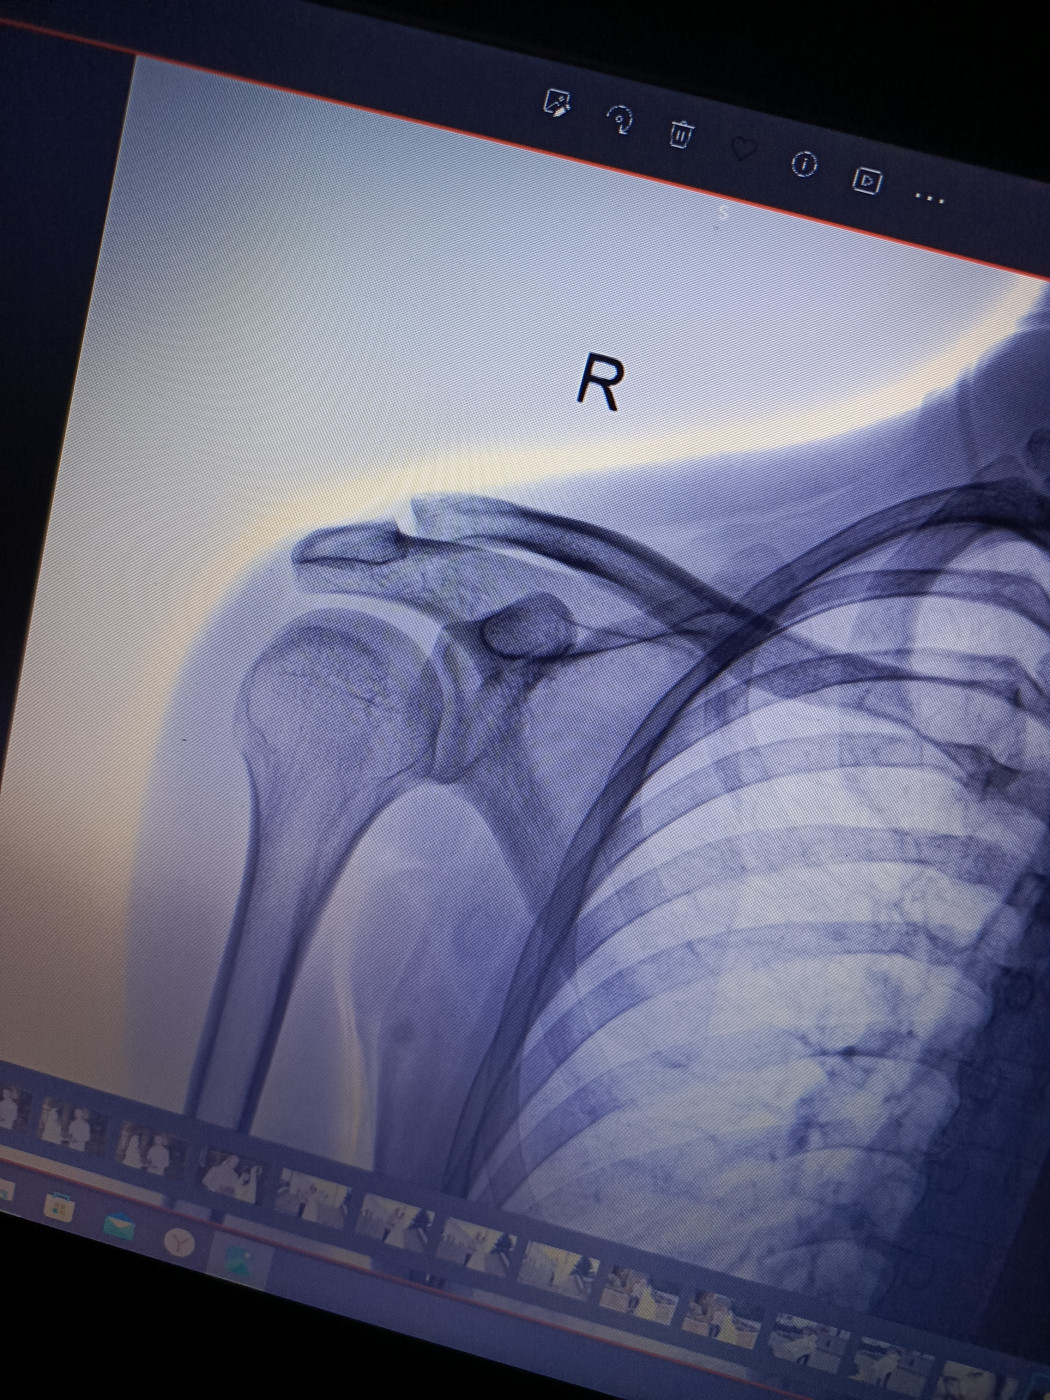

Как лечить, что делать — перелом плеча со смещением и обломками?

Частичный разрыв связок на ключице